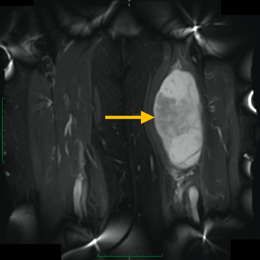

Radiographic imaging is used to help form a diagnosis. These include X-Ray, MRI, CT and Bone Scans

An example of an MRI is shown.